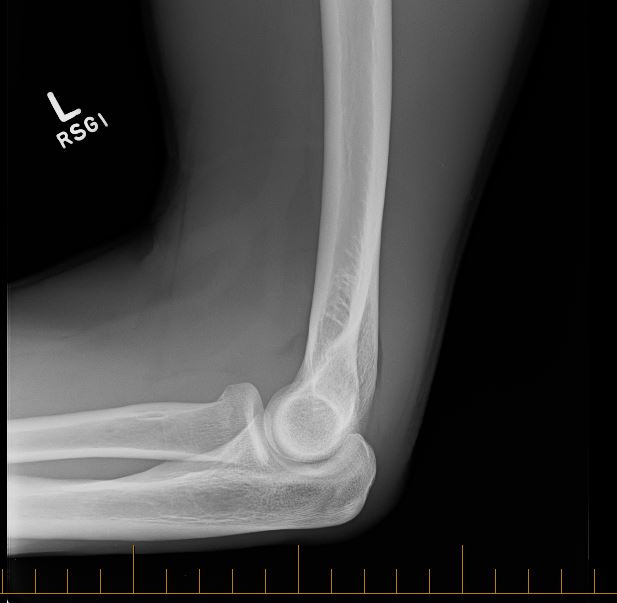

After checking the driver stopped I proceed to check myself over (wow, no blood)! Now the bike, even bigger WOW seems all ok! Both wheels a little out of true, a banged up left pedal, twisted seat and a banged up helmet! Awesome, straighten the seat and lets get home! Driver helped me straighten the seat, cause my left hand was a little sore and I was having problems griping the seal properly. Half way home and I tried to get out of the saddle to climb a little rise, OUCH, my left arm hurt a lot (trying to girp the handle bars)! Finally home (using very tiny gears and seated) and straight to the doctors to get check over! X-rays and neurological assessments complete, result fractured elbow, head OK! Score, NOT! 2 to 4 weeks in a collar and cuff sling, and no riding or running 😦